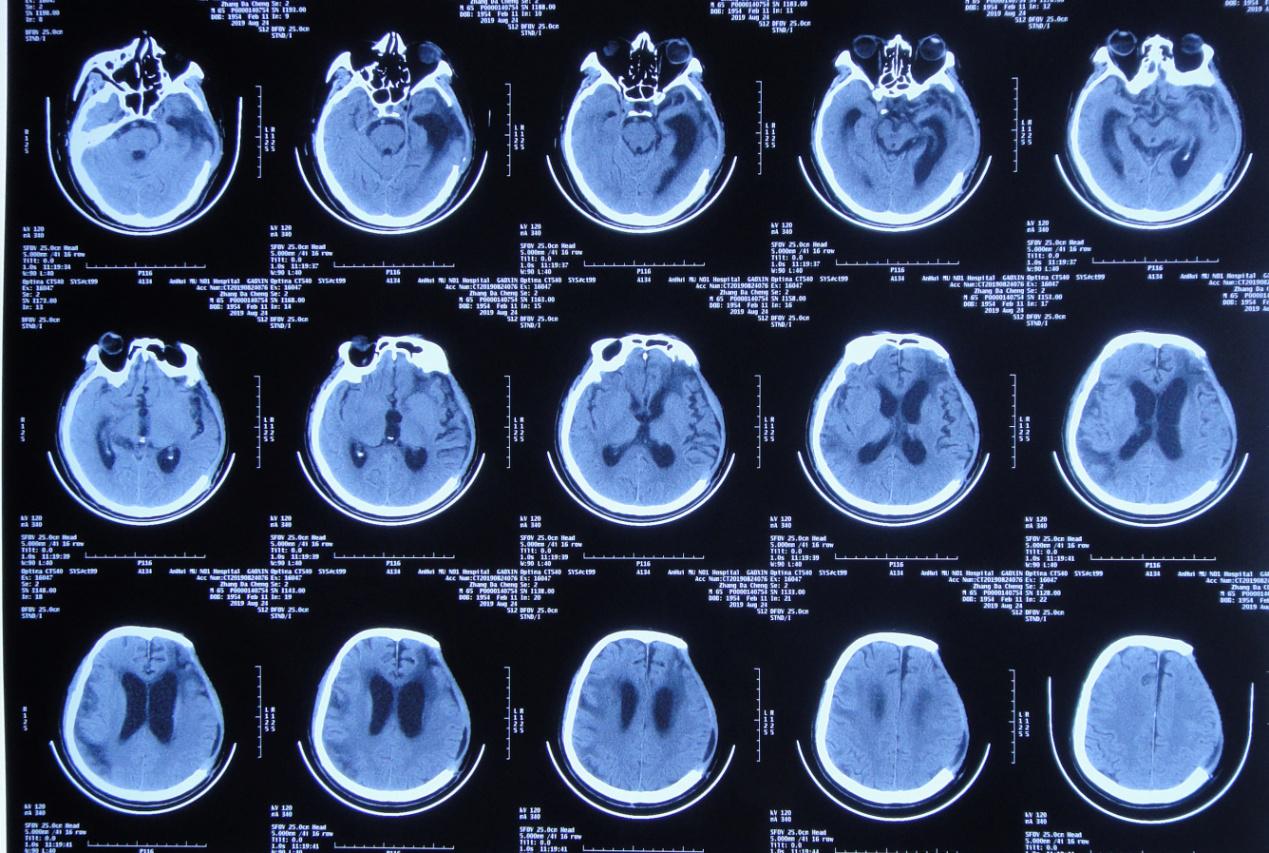

左颞叶血肿清除+去骨瓣减压术后第106天,即2019年 10月24日行颅骨修补术。

颅骨修补术后第5天即2019年 10月29日复查头颅CT( 图-7 )呈颅骨修补术后改变,脑室较前无变化。

图-7: 2019年10月29日术后头颅CT

颅骨修补术后第14天,即2019年 11月8日患者出现双下肢力量反而较前减退(注:本人观点最好不要先补颅骨),行走需1人搀扶,复查头颅CT( 图-8 )示脑室较前无明显变化(但双颞角较前稍扩大)。

图-8: 2019年11月8日头颅CT

医生嘱患者加强康复锻炼,但是双下肢力量反而更逐渐继续减退,且意识也加重,由原来清醒的状态又逐渐变为嗜睡。

患者意识进一步恶化,颅骨修补术后第34天,即2019年 11月28日,患者意识由嗜睡变为昏睡状态,复查头颅CT( 图-9 )示脑室较前稍增大,脑室周围水肿稍加重。

图-9: 2019年11月28日头颅CT

意识逐渐恶化脑室不断扩大,2019年12月4日行右侧脑室钻孔外引流术,术后当日复查头颅CT( 图-10 )呈脑室钻孔外引流术后改变。

图-10: 2019年12月4日术后头颅CT